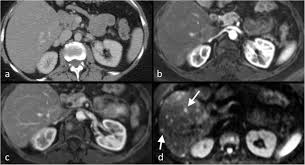

It is sometimes called computerized tomography or computerized axial tomography (cat). I was told that a bone scan is often used for diagnosis whereas ct scans can be used for follow up scans. This test is done because it is common for breast cancer to metastasize to the lungs. Study the brain, spine, chest, abdomen or pelvis find out the size, shape and location of tumours How do ct scans work? When the doctor knows this, they can choose the best course of treatment and maybe even predict your chances of recovery. Metastatic patterns and their prognosis. A trained radiologist will interpret the ct scan images and send the detailed results. If you have a large breast cancer, your doctor may order a ct scan to assess whether or not the cancer has moved into the chest wall. Do ct scans detect breast cancer? Right now, ct scans aren't routinely used to look for breast cancer, but may be used to look at chest, spine, or abdominal problems, such as a herniated disc or lung disease. Benefits of a ct scan. Cas article google scholar 6.

It can damage the dna in your cells and raise the chance that they'll turn cancerous. Additionally, a diagnostic scan only tells part of the story. Metastatic patterns and their prognosis. This test is most often used to look at the chest and/or belly (abdomen) to see if breast cancer has spread to other organs. How do ct scans work? A chest ct scan can detect even smaller nodules in the lung. A ct scan may be done to: Cas article google scholar 6. Scans give doctors the ability to diagnose lung cancer in the earliest stages, which allows for a better cure rate. Ct scans can help doctors: If you have a large breast cancer, your doctor may order a ct scan to assess whether or not the cancer has moved into the chest wall. Ct scans can show a tumor's shape, size, and location. Learn the stage of your cancer.

My bone mets were discovered during a bone scan (i.e. Cas article google scholar 6. Right now, ct scans aren't routinely used to look for breast cancer, but may be used to look at chest, spine, or abdominal problems, such as a herniated disc or lung disease. The contrast helps to show up areas of increased vascularity and so it does help show up tumours as they have a rich blood supply. It is sometimes called computerized tomography or computerized axial tomography (cat).

Ct Provides Best Diagnosis For Novel Coronavirus Covid 19 Imaging Technology News from www.itnonline.com Knowing the stage helps your doctor decide which treatment you need. It is sometimes called computerized tomography or computerized axial tomography (cat). Ct scans can show a tumor's shape, size, and location. The benefits of having a ct scan usually outweigh the risks. Study the brain, spine, chest, abdomen or pelvis find out the size, shape and location of tumours The contrast helps to show up areas of increased vascularity and so it does help show up tumours as they have a rich blood supply. By comparing ct scans done over time, doctors can see how a tumor is responding to treatment or find out if the cancer has come back after treatment. Nuclear) and show up on my ct scans as well.